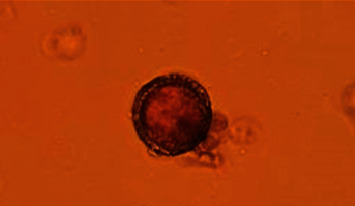

Methods: Based on five municipal districts, 240 soil samples were collected from public parks and playgrounds in Zahedan. The modified Sheather's flotation technique was employed to isolate Toxocara spp. eggs from the soil, followed by microscopic assessment and molecular evaluation of internal transcribed spacer 1 and 2 ribosomal deoxyribonucleic acid (ITS1 and 2 rDNA) using nested polymerase chain reaction (nested PCR) to identify the presence of Toxocara spp. eggs. The Sanger sequence was used to differentiate the Toxocara species. Subsequently, all the sequenced data were blasted and compared with other sequences available in the GenBank.

Results: Out of 240 soil samples collected, 7 (2.9%) samples were identified to contain Toxocara spp. eggs using Sheather's flotation and microscopic techniques. Meanwhile, 19 (7.9%) samples were positive using nested PCR. According to the Sanger sequencing analysis findings, all positive samples were contaminated with Toxocara cati.